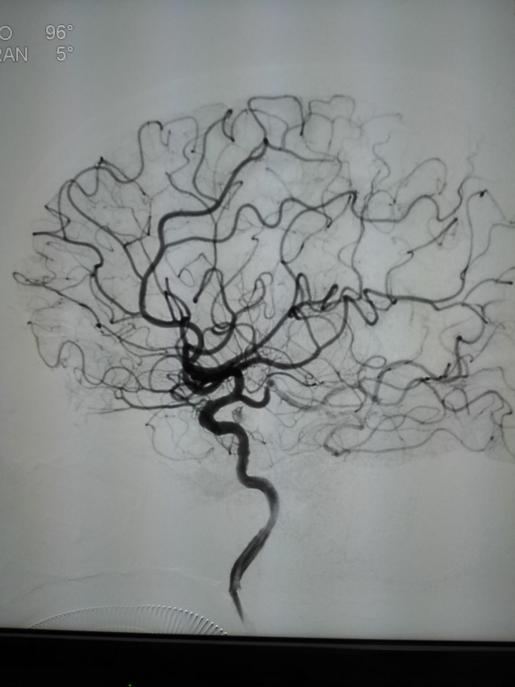

与患者家属沟通后立即于导管室行全脑血管造影术,术中提示右侧颈内动脉末端闭塞,TIMI分级为0分(完全闭塞)。萨仁格日乐主任医师与徐鹏主治医师与患者家属沟通,考虑患者发病特点,行支架取栓术。术中利用取栓支架(Solitaire 4mm×20mm)反复通过闭塞处取栓,前后共五次,最终手术成功,患者闭塞处血运再通。

手术相关图片:

术前侧位 术后侧位